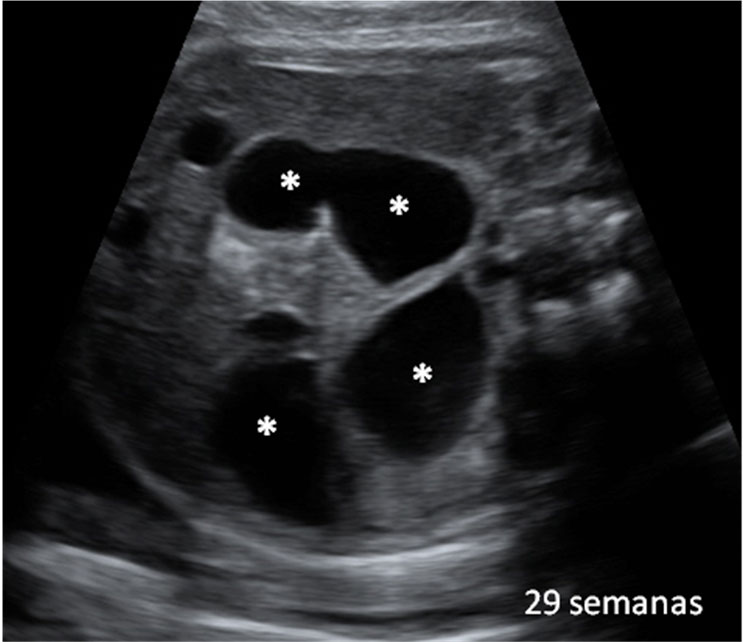

Mediante el ultrasonido, se mide el diámetro biparietal

Con una edad gestacional de 20 semanas, este bebé está muy entretenido con un dedo en la boca. En esta ecografía de la semana 20, la morfológica, el especialista también mide el diámetro parietal del feto para comprobar su correcto desarrollo.